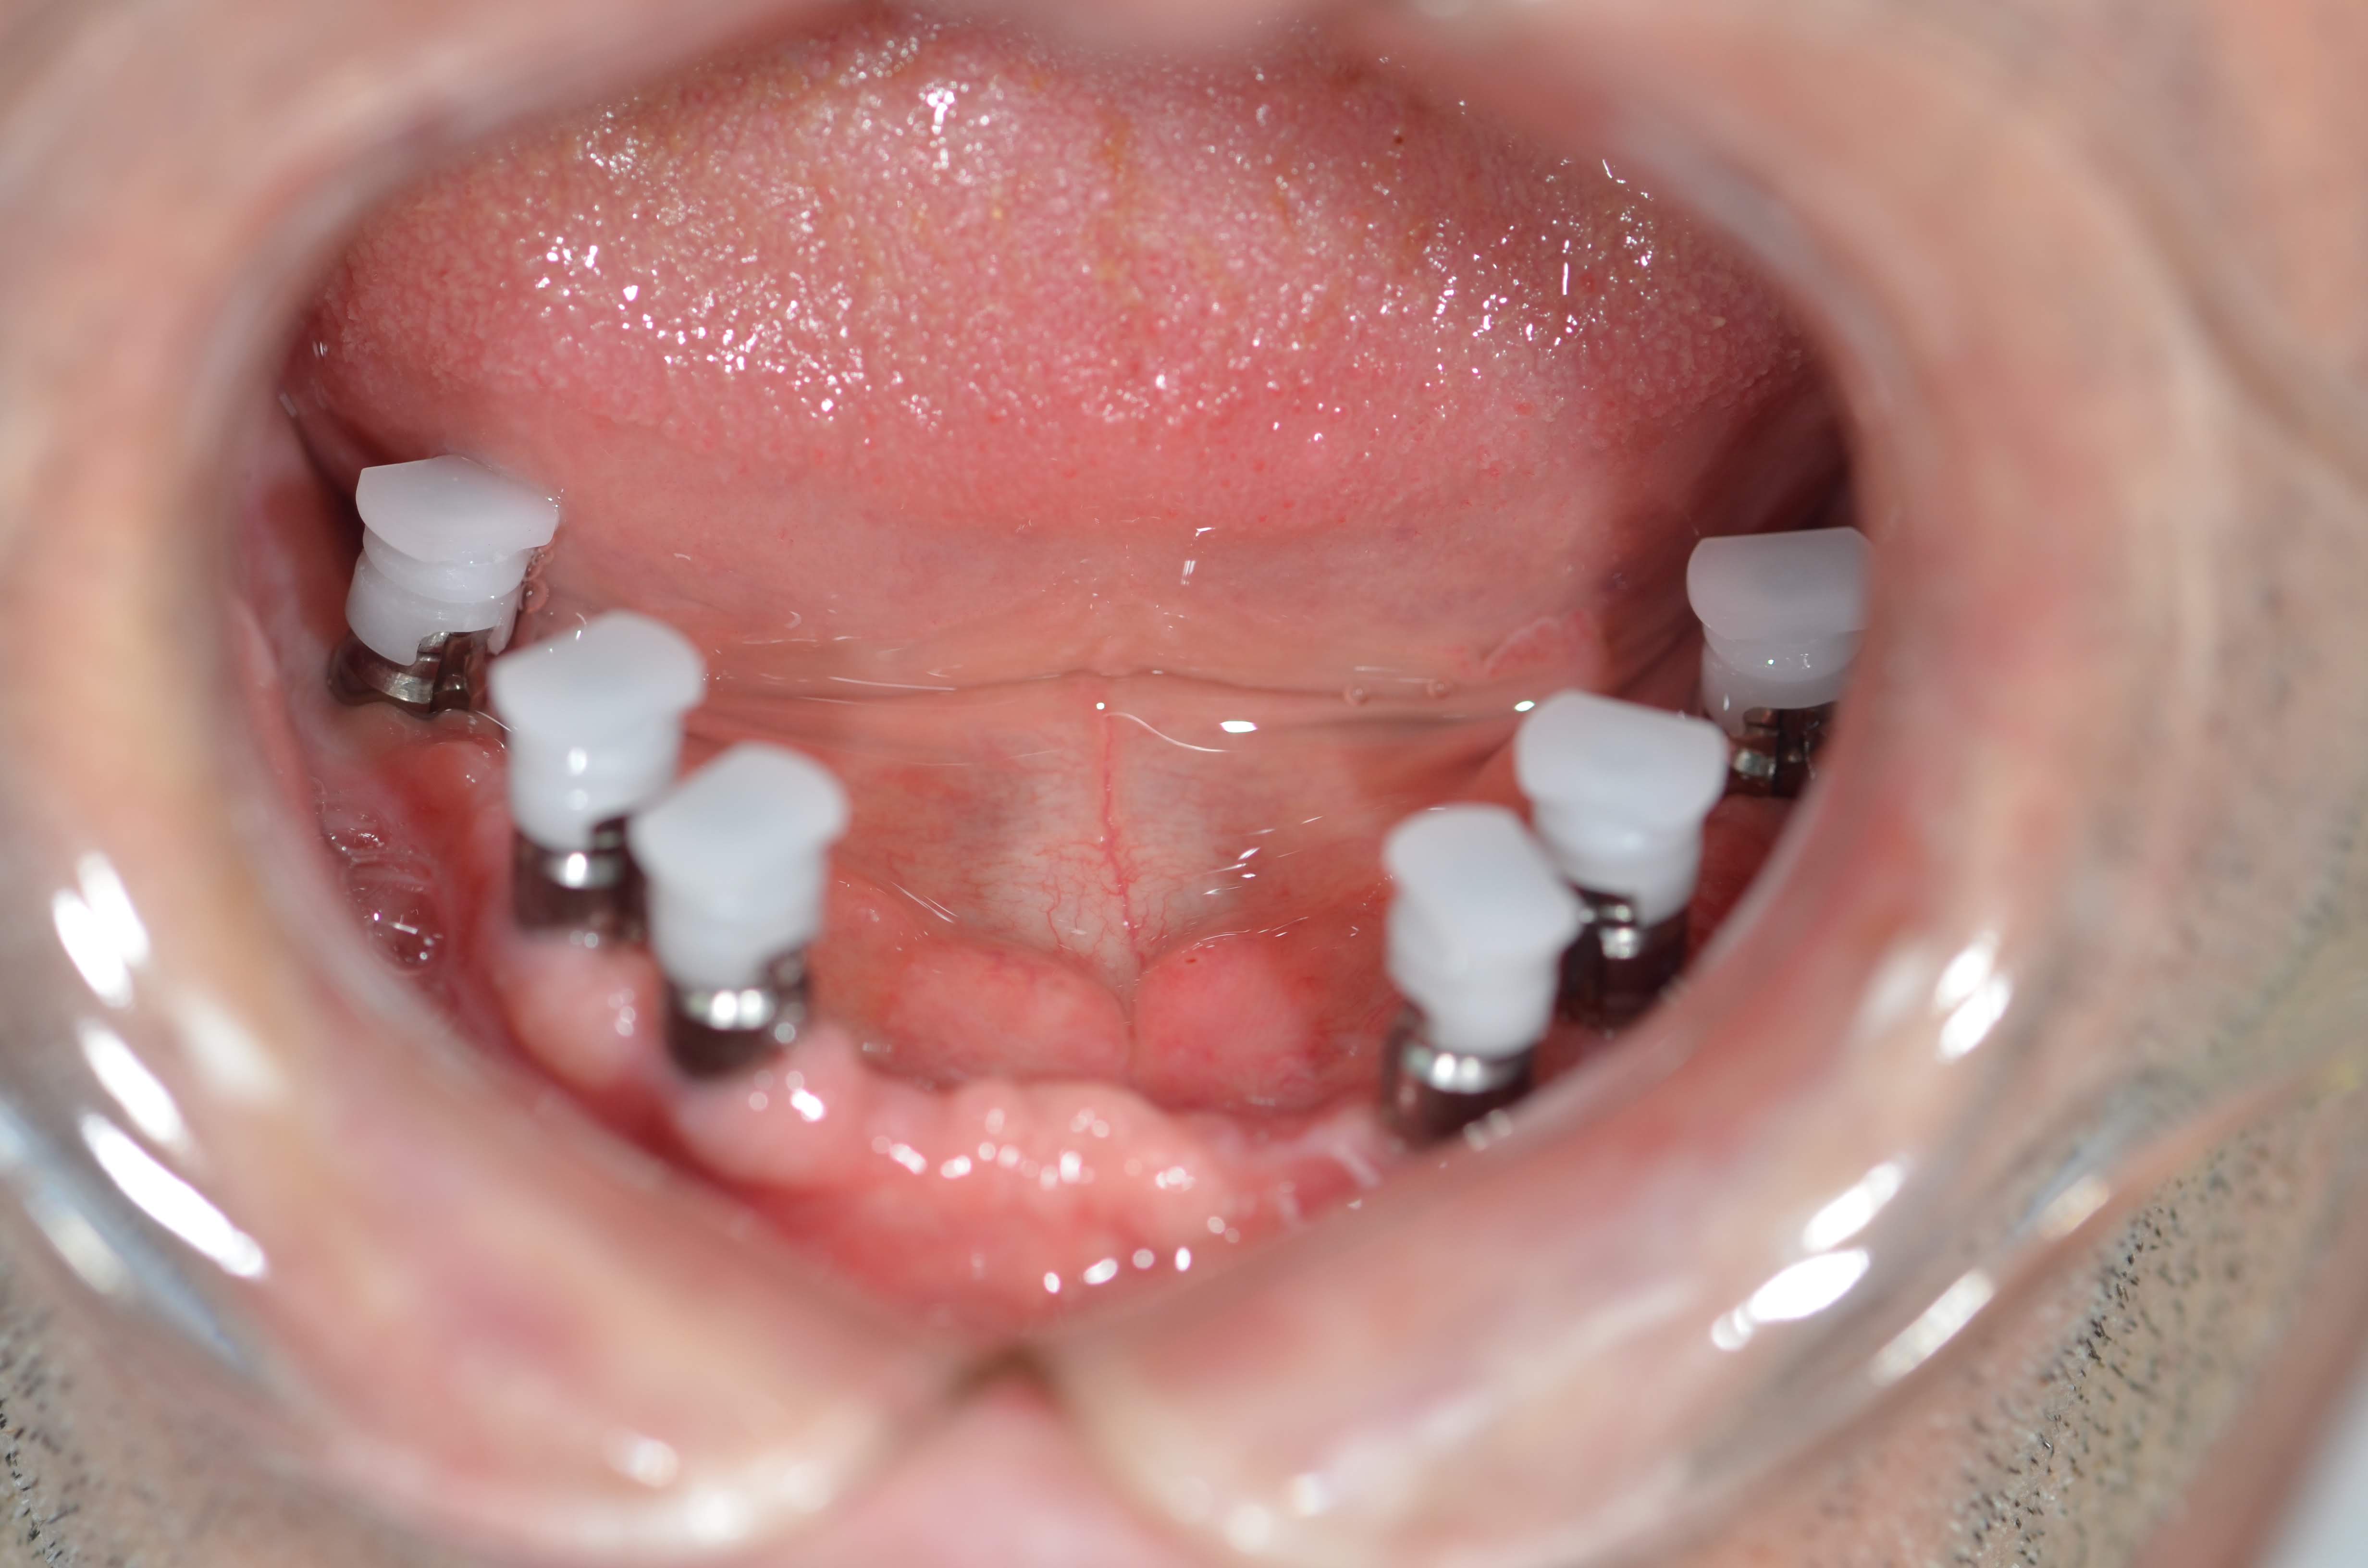

alt çene 4 implant üzeri protez çıt çıtlı

alt çene 6 implant ölçü aşaması